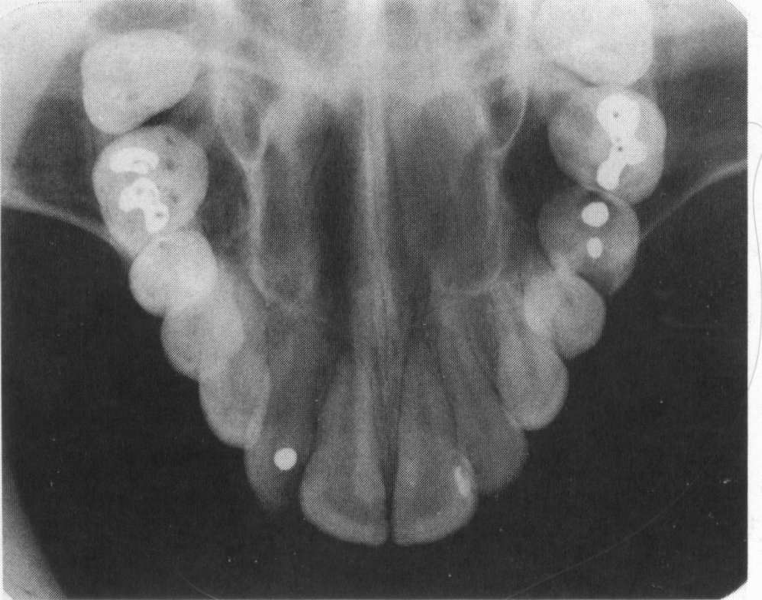

Cross-sectional Technique

yields more information about tori, impactions, and malpositioned teeth. It will also show calcifications in soft tissues, ie. Salivary gland stones or calcifying cysts.

Cross-Sectional Radiograph